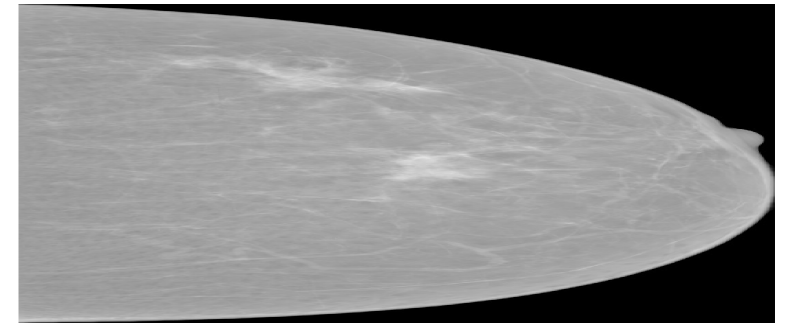

As data augmentation, random Gaussian noise (μ=0\mu=0, σ=0.005\sigma=0.005), random horizontal flipping (p=0.5p=0.5), random rotation (15-15^{\circ}, +15+15^{\circ}), random translation (0, 0.1), random shearing (25-25^{\circ}, +25+25^{\circ}), scaling by a random factor between 0.8 and 1.6 were used. Three standardized mammography images from different datasets are shown in the Figure 6.

Refer to caption

(a) Hacettepe

(b) VinDr

(c) CSAW

Figure 6: Standardized mammography samples from Hacettepe, VinDr, and CSAW dataset.